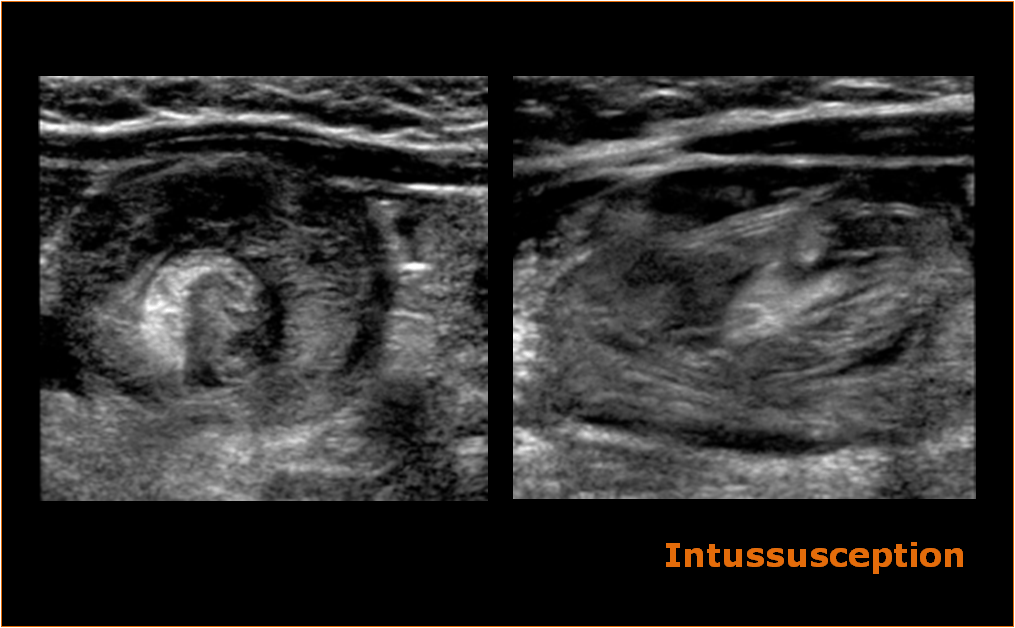

The target sign of intestinal intussusception, also known as the doughnut sign or bull's eye sign.

The appearance is generated by concentric alternating echogenic and hypoechoic …

The appearance is generated by concentric alternating echogenic and hypoechoic … target sign intussusception. The sail sign on an elbow radiograph, also known as the anterior fat pad sign, describes the elevation of the anterior fat pad to create a silhouette similar to a billowing spinnaker sail from …